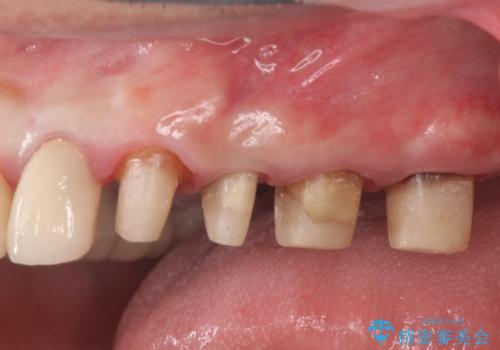

虫歯だらけの歯を治療したい

- 「虫歯が多発し、治療が終わらない。歯も無くなったし今後悪くならないような治療をしたい。」と精密治療を希望され来院されました。

虫歯の徹底的な除去やセラミック補綴、精密根管治療、歯周外科を行うことで、治療後に歯磨きがしやすく、かみやすい機能的な仕上がりへと導きます。

歯周外科手術をおこなったことでフェルールも獲得でき、破折リスクをより抑えることにも成功しています。